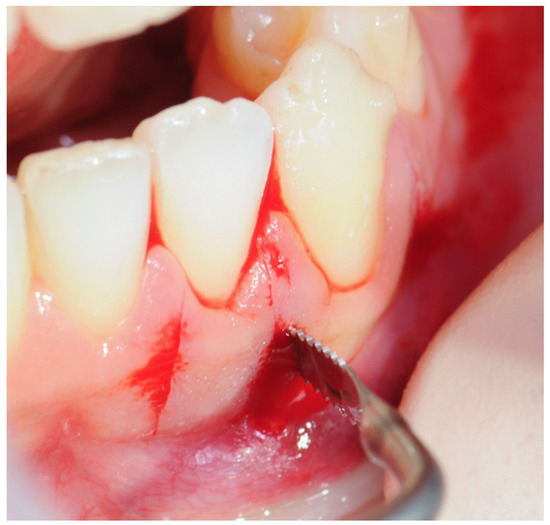

2.3. Surgical Procedure

2.3.1. Example—Anterior Open-bite